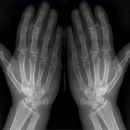

Hände nach Norgaard (Rheuma-Spezialaufnahme in der Medizin)

Lagerung

Pat. sitzt frontal am Tisch, Ellenbogen möglichst zusammen, Handinnenflächen zeigen nach oben, Finger leicht abgespreizt und gestreckt, Unterarm zur Tischoberfläche im Winkel von ca. 30° (-45°) (Ballauffang- o. Schalenhaltung). Beide Hände gleichzeitig zum Vergleich in einem Strahlengang.

Zentralstrahl

Senkrecht auf Kassettenmitte.

Anmerkung

Gute Projektion der kleinen Gelenke und Gelenkspalten.

Qualitätskriterien

Guter Einblick in die Gelenke.